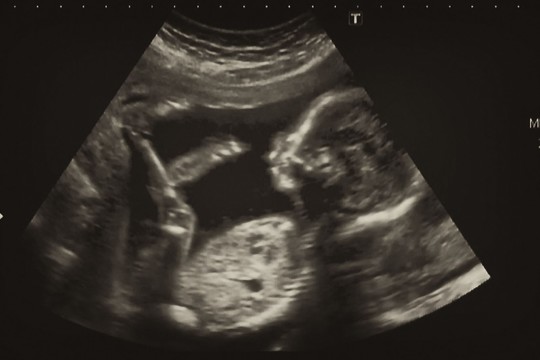

Vieno kūdikio netekusi moteris nė neįtarė, kas jos gimdoje